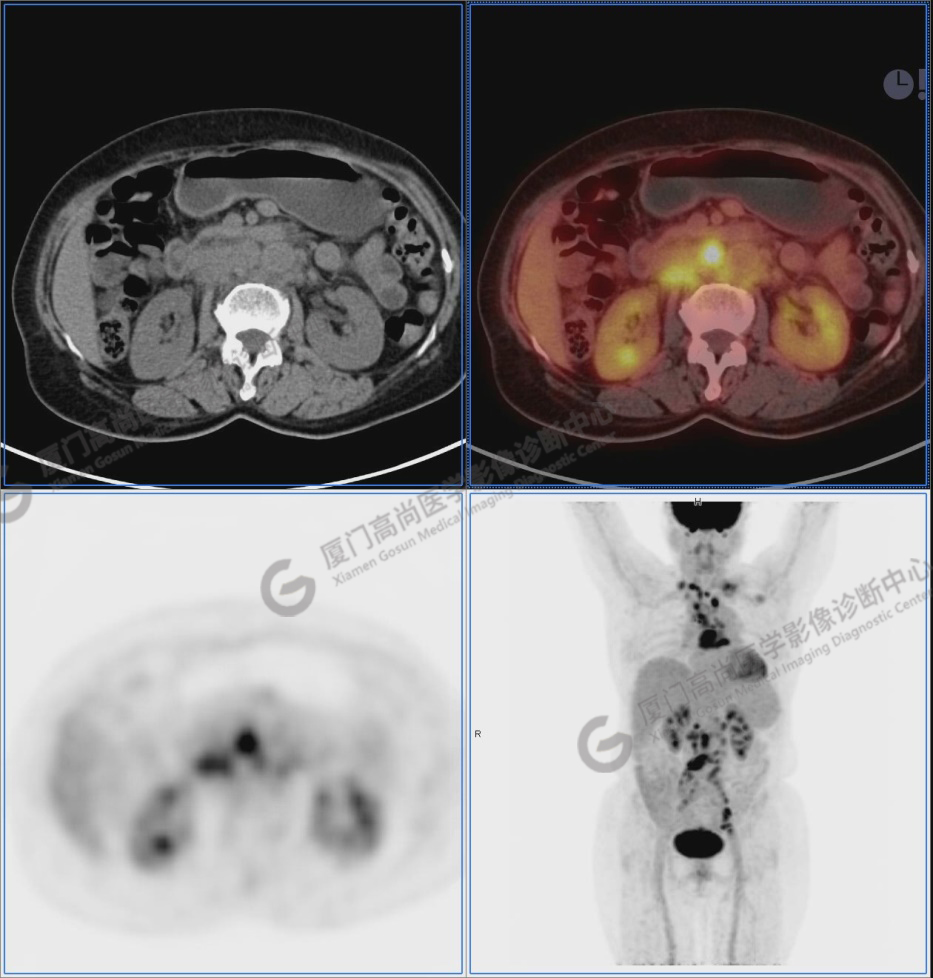

圖1:PET/CT全身圖像

圖2-9:雙側(cè)鎖骨區(qū)、縱隔、右側(cè)內(nèi)乳區(qū)、腸系膜緣、腹膜后、雙側(cè)髂血管旁及盆腔多發(fā)腫大淋巴結(jié)影,代謝不同程度增高,考慮為轉(zhuǎn)移。

圖10-11:子宮頸軟組織腫塊,代謝異常增高,考慮為宮頸癌。

圖10

圖12-13:延遲2小時后,宮頸腫塊糖代謝進一步增高。